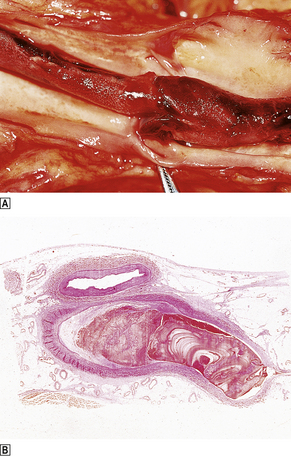

image

Fig. 8.3 Venous thrombus. image Femoral vein opened at autopsy to reveal a thrombus. image Histological section showing the characteristic laminated or coralline structure of a thrombus.